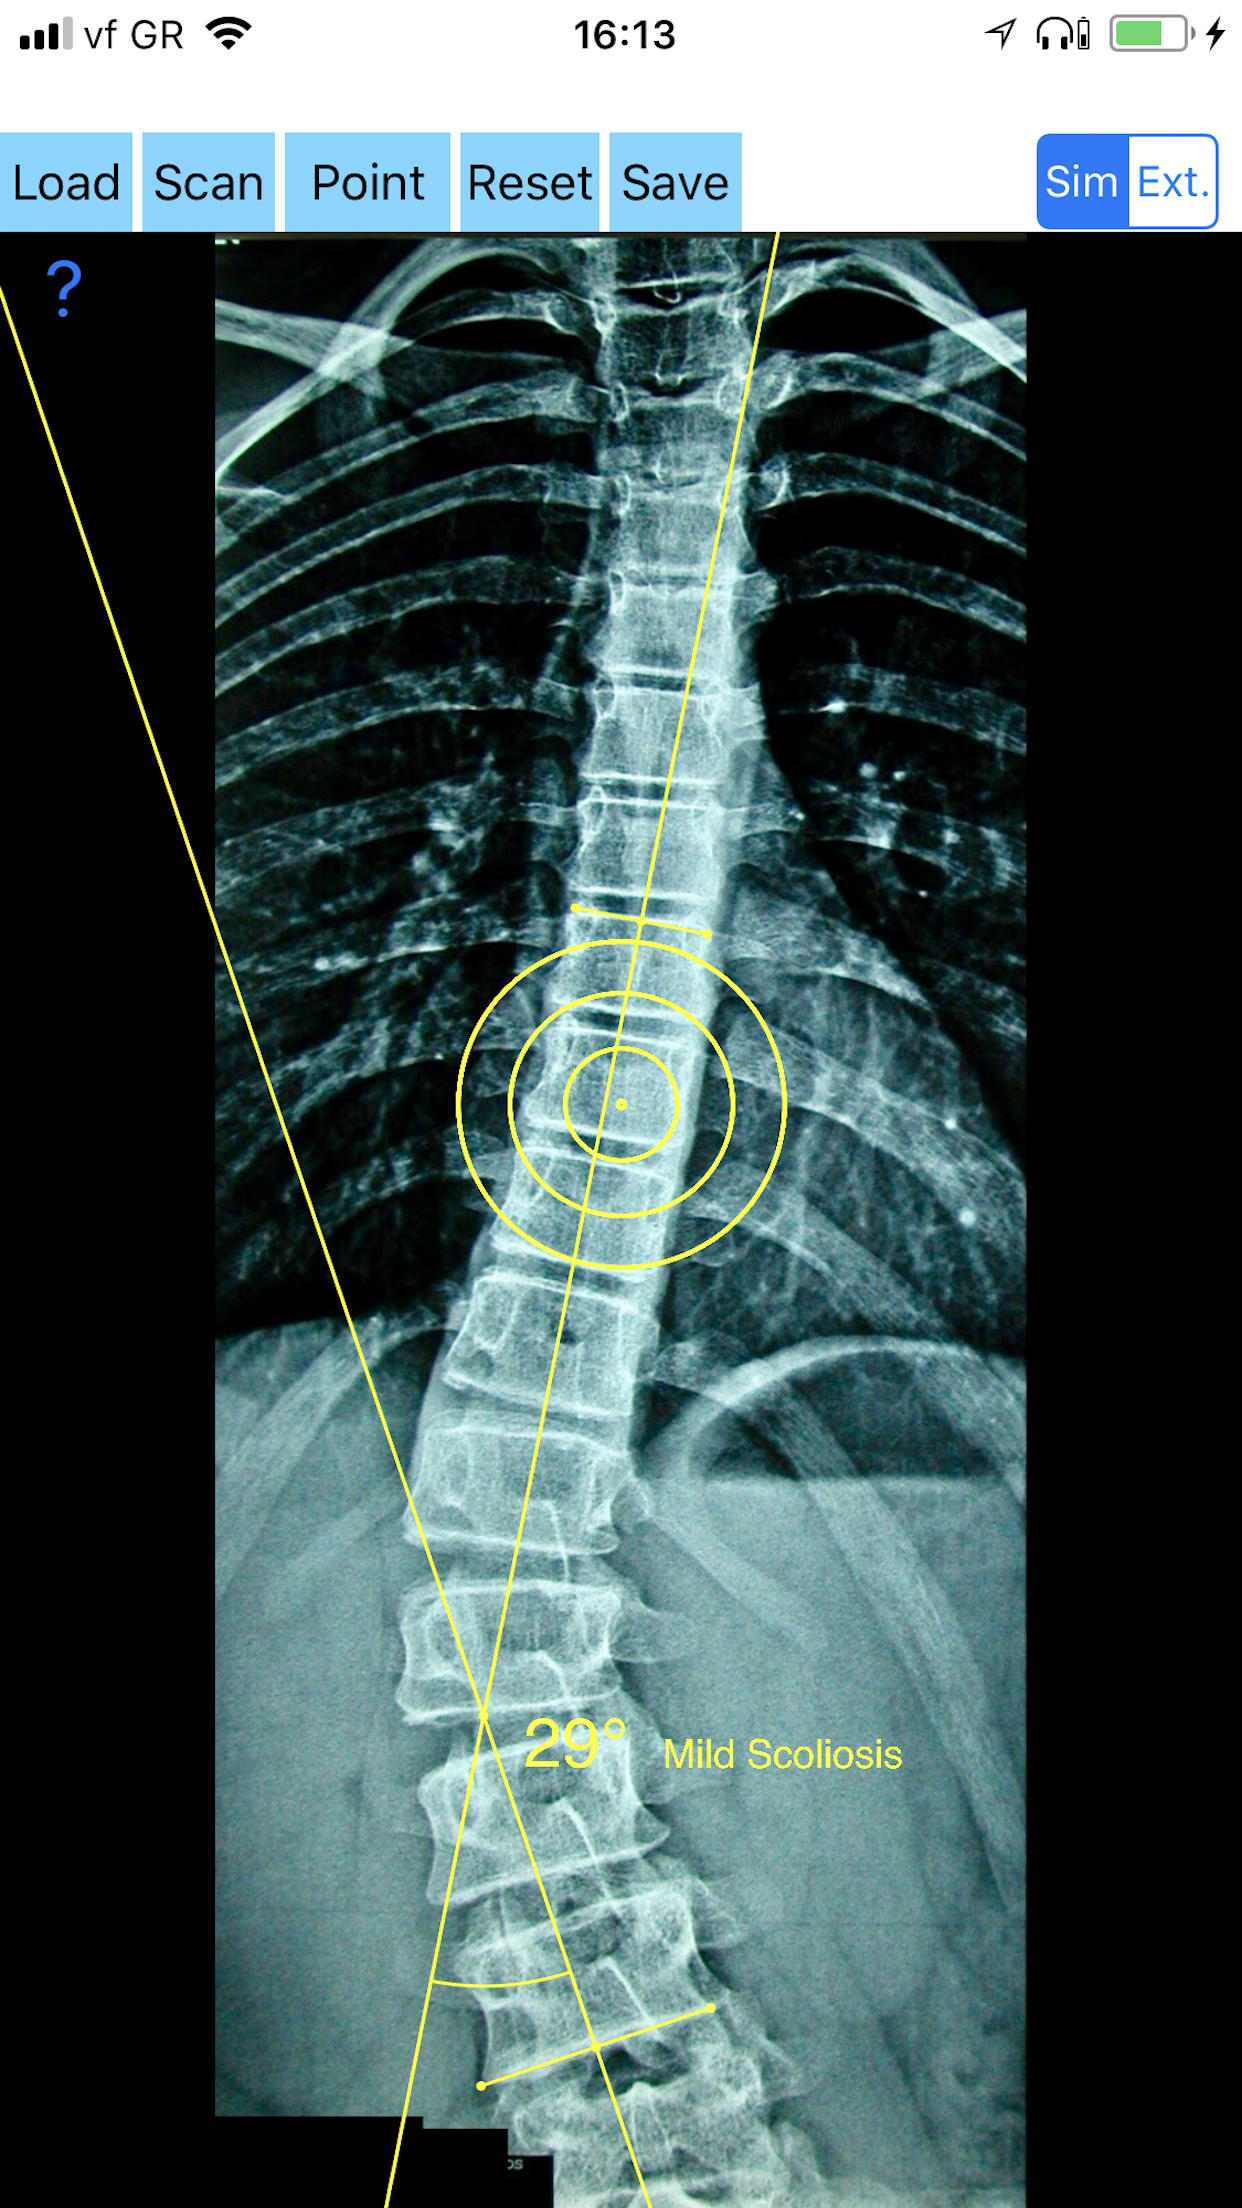

9 useful apps for the orthopaedic surgeon ready to help in clinal settings .... .The Apps are a great idea and a novel integration of technology that uses the camera, touch screen, and computational power to help surgeons measure someone x-rays and without a protractor, this app can provide an objective measurement for an otherwise subjective assessment. Apps calculates the angles and presents them on the initial drawing with the option to save the image. App that save money and effort to orthopaedic surgeons in everyday clinical settings. You can take a photo of x-rays images of the patient in you mobile phone or tablet, the App simply guides you to do the rest. It is really a handy tool to the medical doctor. Protractors, well-sharped pencils, are obsolete for measuring patients X-Rays! These apps are not a simple goniometer or ruler, are enhanced products. End with protractors, rulers and texts books forget cumbersome measurements by few clicking in your screen you have results with suggestive diagnosis.......because the build in databases based in international reference databases compares the measured data with the Databases. All information received from the softwares output must be clinically reviewed regarding its plausibility before patient treatment! The Orthopaedic Tool Box Apps indicated for assisting healthcare professionals. Clinical judgment and experience are required to properly use the software. The software is not for primary image interpretation Please visit www.orthopractis.com or in iTunes